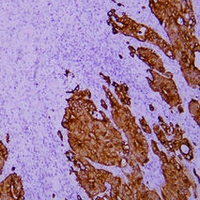

(Immunohistochemical analysis of Cytokeratin 18 staining in human hepatocellular carcinoma formalin fixed paraffin embedded tissue section. The section was pre-treated using heat mediated antigen retrieval with sodium citrate buffer (pH 6.0). The section was then incubated with the antibody at room temperature and detected using an HRP conjugated compact polymer system. DAB was used as the chromogen. The section was then counterstained with haematoxylin and mounted with DPX.)